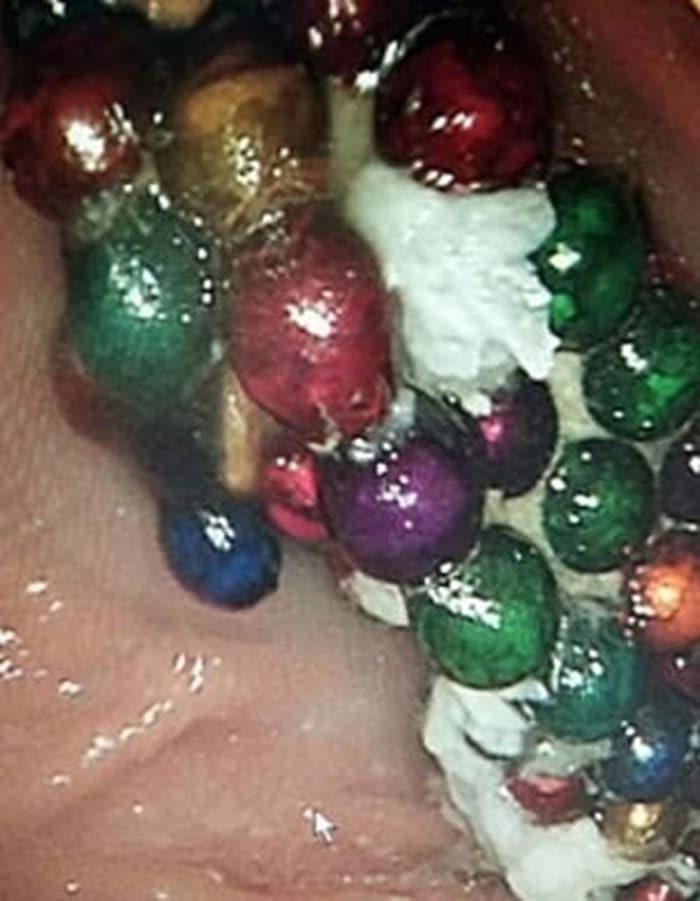

Mıknatıslı olan bilyeler çocuğun midesinde biraraya gelerek büyük bir kitle haline geldi. Bilyeler doğal yollardan çıkmayınca küçük kız 2 ay bu kitleyle yaşadı. Doktorlar rontgenle tespit ettikleri kitleyi ameliyatla çıkardı.